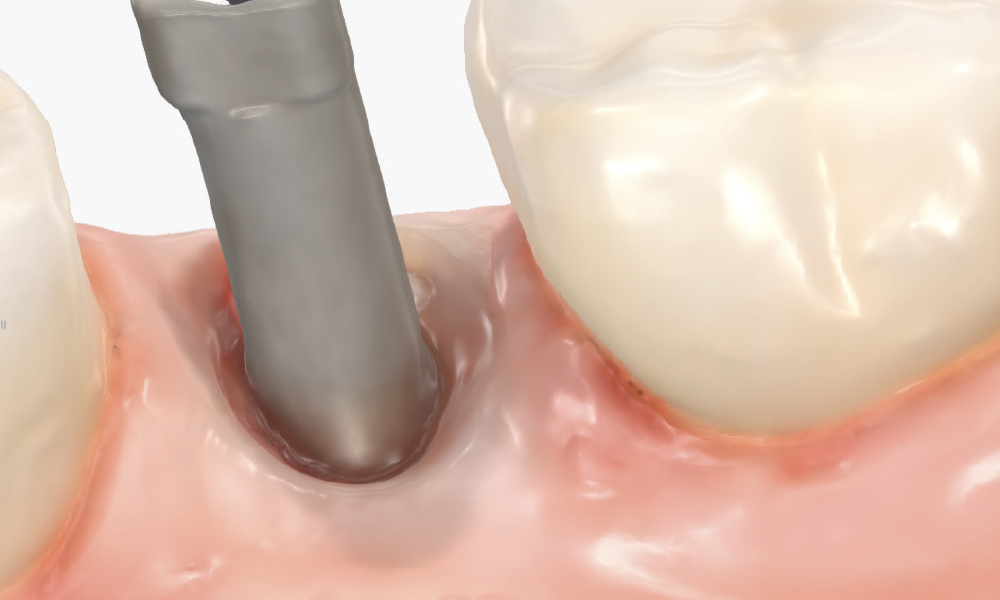

Thoroughly Scan the Scan Body Geometry

Thoroughly Scan the Scan Body Geometry. Complete, high-resolution capture of the scan body is non-negotiable. This is how laboratory software determines the precise three-dimensional position and angulation of the implant. The software matches the scanned scan body with its library file to establish the implant location in space. Scan from multiple angles to ensure all identifying features and surfaces are captured, as incomplete scan body data leads to misaligned restorations regardless of how perfect the rest of the scan appears. Verify that all reference markers, grooves, or geometric features are clearly visible in the acquired scan.

Capture the Surrounding Soft Tissue Immediately

Capture the Surrounding Soft Tissue Immediately. Scan the peri-implant soft-tissue architecture as soon as the scan body is placed, before the tissue collapse occurs. Gingival tissues begin to collapse and distort within minutes of scan body insertion, and the initial tissue contours are critical for creating proper emergence profiles. Work efficiently but thoroughly to document the tissue topography in its most accurate state.